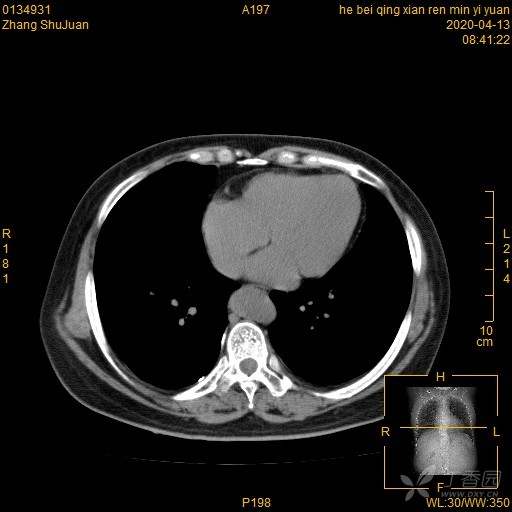

右肺结节猜病理,有结果(得细心,这个很有意思)(俱乐部3)

西门开心 +5 丁当患者性别:女

患者年龄:49

简要病史:体检发现右肺结节,不吸烟。

体格检查:无阳性体征

辅助检查:血常规、血沉正常,血肿瘤标志物正常。FET-CT倾向恶性结节

临床诊断:右肺结节

治疗经过:手术

大家猜猜病理是什么?